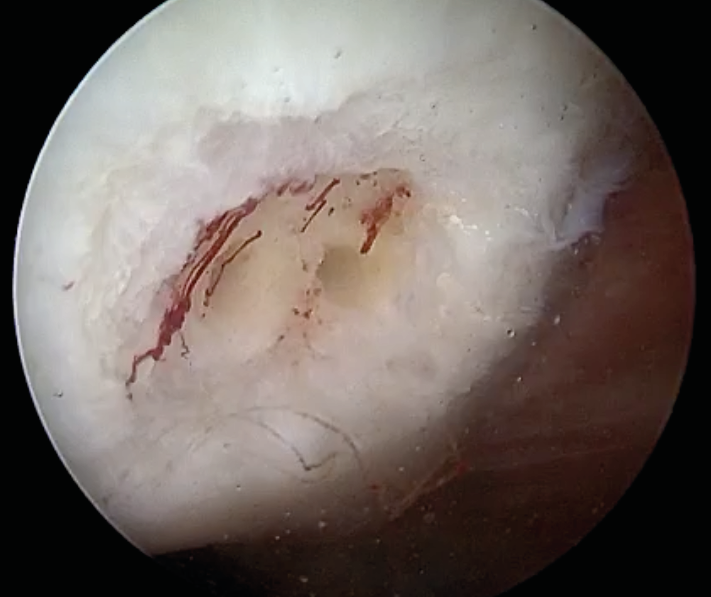

The old adage “hyaline cartilage does not repair” continues to hold true and should be communicated to patients, despite all modern cartilage restoration procedures. Whilst all surgery tech-niques including the latest generation of modern autologous chondrocyte transplantation (ACT) allows replacing the cartilage defect with a similar, histologically high-quality (hyaline-like) structure, this transplant is not identical to natural cartilage (Fig 3).